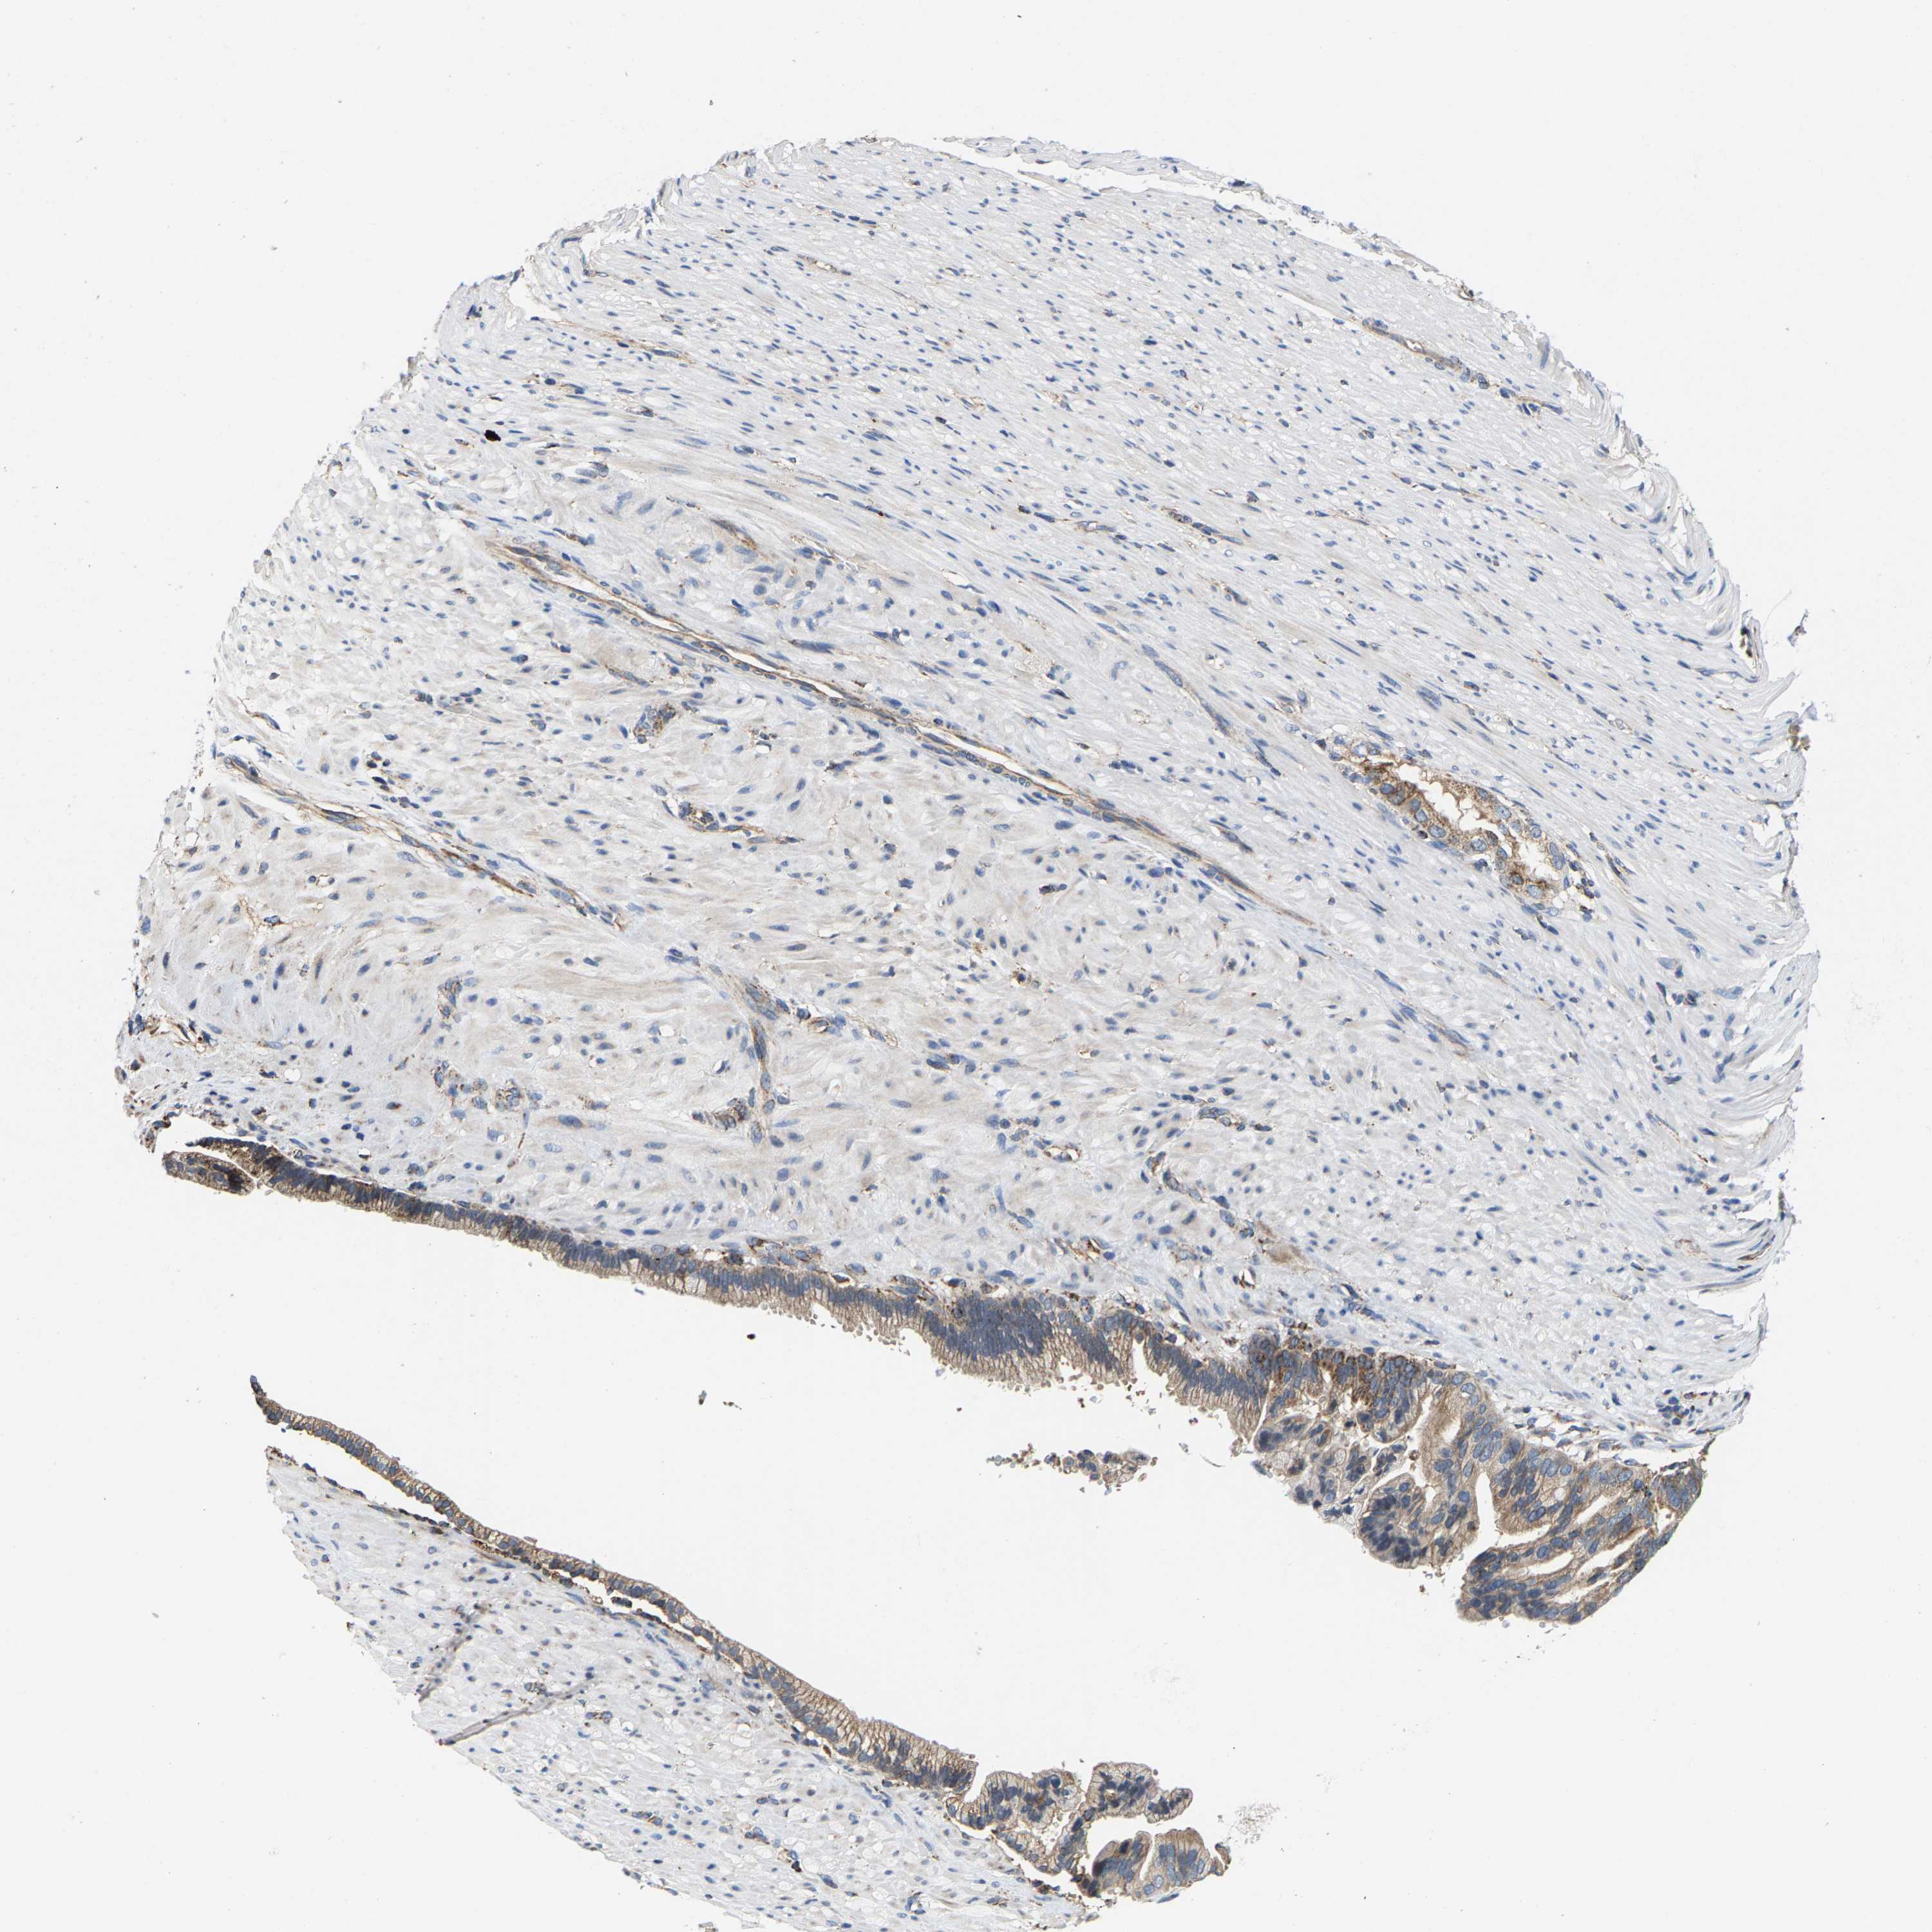

PANCREATIC CANCER - Protein expressioni

A mouse-over function shows sample information and annotation data. Click on an image to view it in a full screen mode. Samples can be filtered based on level of antibody staining by selecting one or several of the following categories: high, medium, low and not detected. The assay and annotation is described here.

Note that samples used for immunohistochemistry by the Human Protein Atlas do not correspond to samples in the TCGA dataset.

Antibody stainingi

Antibody staining in the annotated cell types in the current human tissue is reported as not detected, low, medium, or high, based on conventional immunohistochemistry profiling in selected tissues. This score is based on the combination of the staining intensity and fraction of stained cells.

Each image is clickable and will lead to virtual microscopy that enables deeper exploration of all samples and also displays staining intensity scores, fraction scores and subcellular localization as well as patient and tissue information for each sample.

Antibody HPA020543

Antibody HPA020549

Adenocarcinoma, NOS